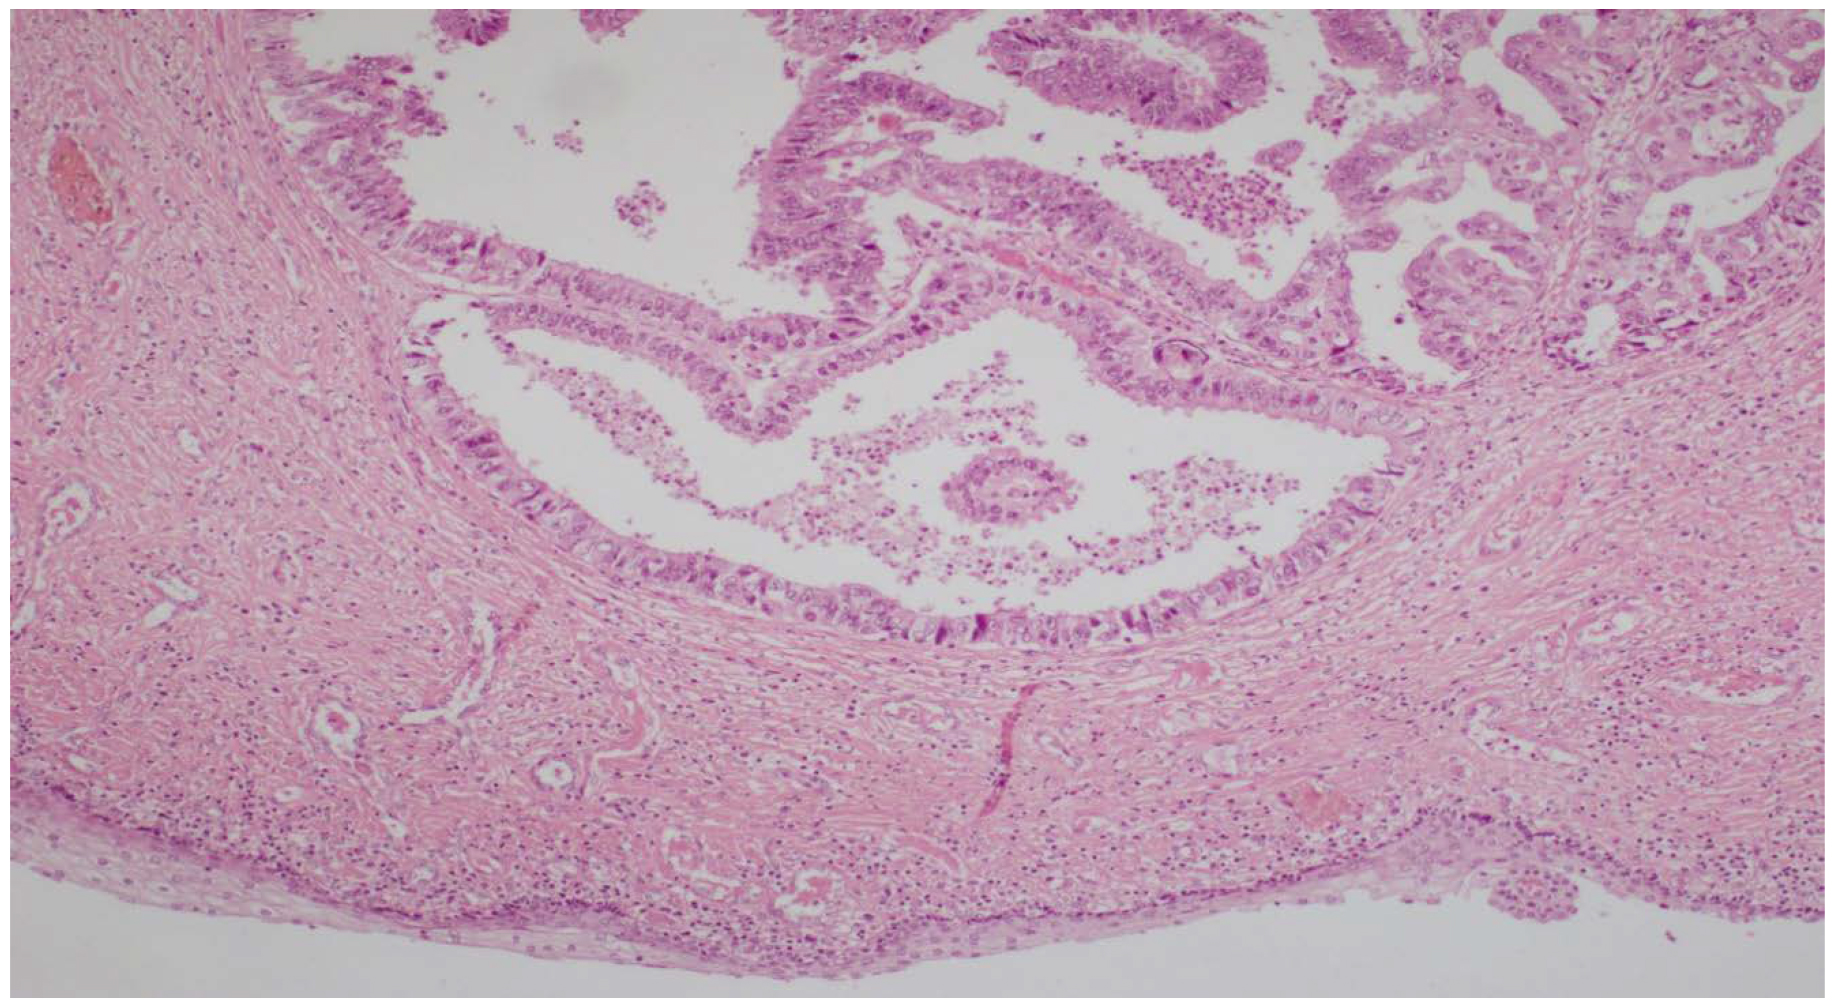

Para el diagnóstico, y dada la facilidad de acceso, se decidió la toma de una citología mediante punción aspirativa con aguja fina (PAAF) de la lesión umbilical, cuyo análisis por parte del servicio de anatomía patológica institucional evidenció positividad para células neoplásicas y así se definió un carcinoma pobremente indiferenciado (figura 3).

Figura 3. Histopatología del ganglio linfático. Infiltración por células neoplásicas de un carcinoma pobremente indiferenciado (hematoxilina-eosina, aumento de 20X)